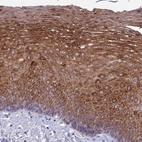

Immunohistochemistry analysis in human esophagus and colon tissues using Anti-TMEM40 antibody. Corresponding TMEM40 RNA-seq data are presented for the same tissues.